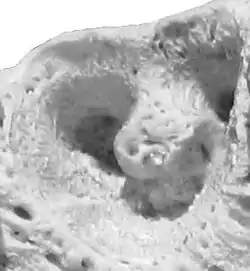

![]() Alveola of the second premolar tooth in a bovine maxillary bone | |

Dental alveoli (singular alveolus) are sockets in the jaws in which the roots of teeth are held in the alveolar process with the periodontal ligament. The lay term for dental alveoli is tooth sockets. A joint that connects the roots of the teeth and the alveolus is called gomphosis (plural gomphoses). Alveolar bone is the bone that surrounds the roots of the teeth forming bone sockets.

In mammals, tooth sockets are found in the maxilla, the premaxilla, and the mandible.